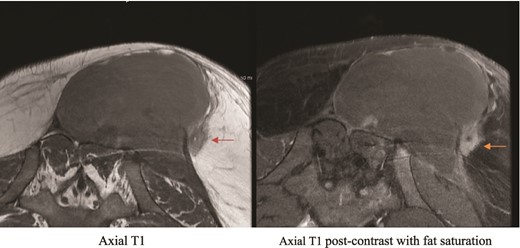

All pathology and culture results were inconclusive, and the patient kept having a drop in Hg, which was managed by blood transfusion. We then proceeded with CT angiogram to delineate the blood supply of the area and to look for possible contrast extravasation, which came back negative. MRI was then requested to rule out soft tissue masses. The MRI result came with unspecific findings but when compared with previous MRI taken in the private hospital, there was slight interval change and a suspicious area, and so interventional radiology were involved to take a deep ultrasonography guided biopsy (Figs 2 and 3).

MRI showing suspicious lesion. Postoperative MRI images show re-demonstration of suspicious lesion when correlated to prior MRI from private hospital. The lesion shows low T1 signal intensity (orange arrow), and post-contrast enhancement with central linear area of non-enhancement.